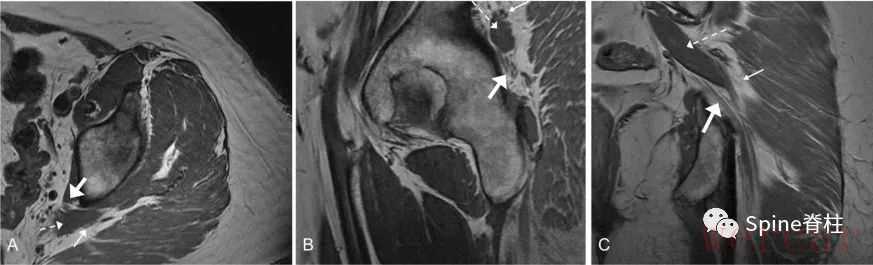

图示:MRI T1像的Beaton-Anson 1型(最常见的坐骨神经解剖,被认为是正常型)。坐骨神经的胫神经与腓总神经部分(细箭头)位于梨状肌(虚箭头)的前面。轴位(A)、矢状位(B)和冠状位(C)平面。